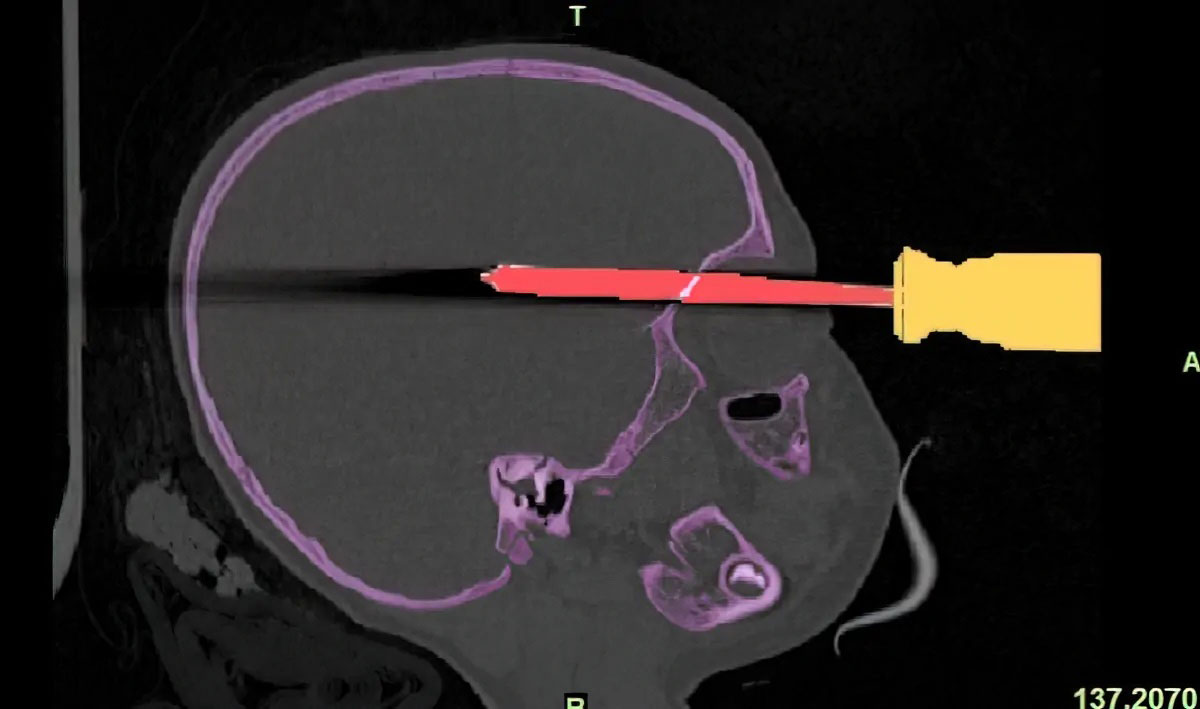

Unsettling pictures, shown as exhibits of the injured or deceased, tend to arouse an emotional response in a courtroom and spark prejudice in jurors. Once a jury becomes biased, they can no longer objectively see the evidence. For instance, an image of a child with a screwdriver stabbing into her eye is shudder-inducing, but the creation of an exact anatomical replica removes a lot of that shock.

The model shows all relevant case information and arouses less emotion than a photo. A medical model can be held and rotated for a complete view of the wound and the size of the skull truthfully represents the child’s age. These courtroom exhibits grant an unbiased opinion by sterilizing shocking evidence.